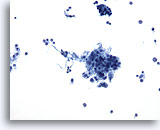

Figure 80

Neck FNA, plasmacytoma.

Single cells with abundant cytoplasm and an eccentric nucleus are present. 20x

Neck FNA, plasmacytoma.

Single cells with abundant cytoplasm and an eccentric nucleus are present.

20x